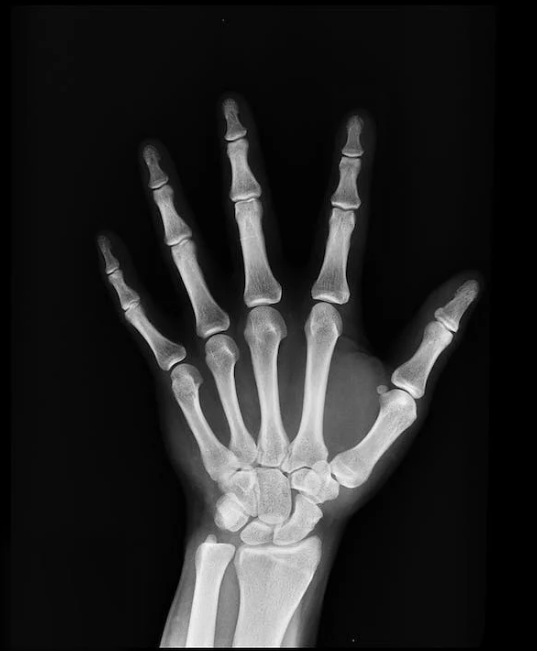

손가락 관절을 움직일 때마다 손가락이 아리고 아프신가요? 이게 손가락 관절염 초기증상이라 걱정되시죠? 대부분 손가락 관절염 증상의 큰 원인으로는 나이가 들면서 몸의 연골이 자연스럽게 마모되기 때문인데요.

이로 인해 관절의 충격 흡수 능력이 감소하여 결과적으로 손가락 관절 통증이 발생할 수 있다고 합니다.